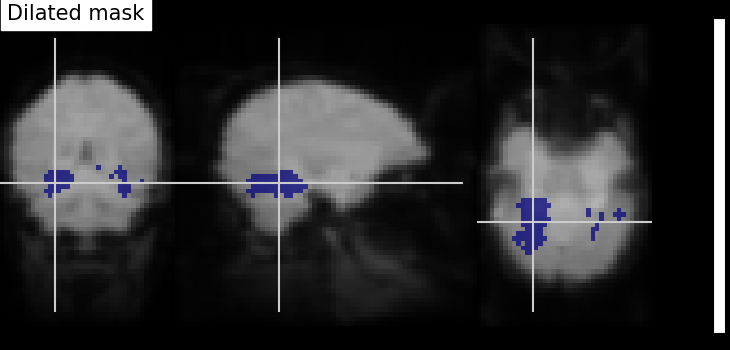

Dilation - Thresholded functional brain images often contain scattered voxels across the brain. To consolidate such brain images towards more compact shapes, we use a morphological dilation. This is a common step to be sure not to forget voxels located on the edge of a ROI. In other words, such operations can fill “holes” in masked voxel representations.

from scipy.ndimage import binary_dilation

# Input here is a binarized and intersected mask data from previous section

dil_bin_p_values_and_vt = binary_dilation(bin_p_values_and_vt)

# Now, we visualize the same using `plot_roi` with data being converted

# to Nifti image.

# In all new image like, reference image is the same but second argument

# varies with data specific

dil_bin_p_values_and_vt_img = new_img_like(

fmri_img, dil_bin_p_values_and_vt.astype(np.int32)

)

# Visualization goes here without 'L', 'R' annotation and coordinates being the

# same

plot_roi(

dil_bin_p_values_and_vt_img,

mean_img,

title="Dilated mask",

cut_coords=cut_coords,

annotate=False,